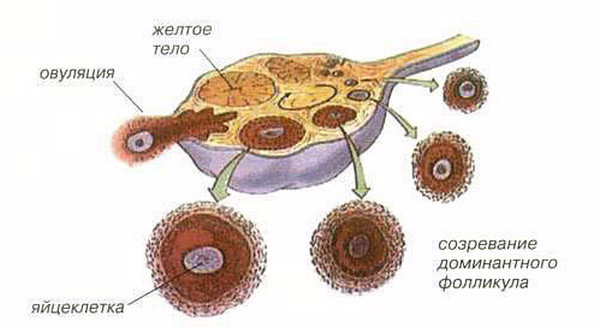

Созревание фолликула в яичнике: этапы и процессы